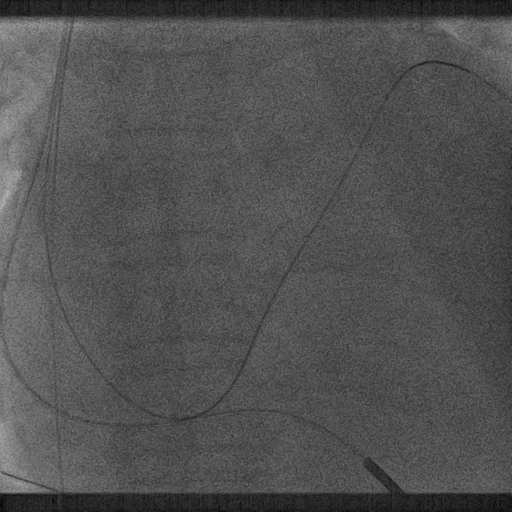

鞘中鞘进入靶血管

超选造影